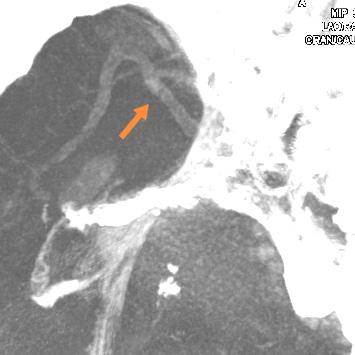

老人家进入医院全面评估后,发现右侧颅内一个主血管存在多节段局限性卡脖子的狭窄,TTP较对侧明显延长,呈缺血状态………,医院多学科讨论评估后,给予第一次外科干预后,患者瘫痪的肢体活动有改善,家人很开心……;在第二次干预之前,又出现了小的新发脑梗塞,继续药物保守治疗,可能还会梗塞;外科干预吧,刚刚出现新发的梗塞,出血风险大,况且又是高龄老年人,血管条件都是个未知数………。本来计划好的二期干预方案受到挑战,面对两难尴尬境地,所有的家人都一时难以决定:向左走?向右走?还是原地踏步进行观望?